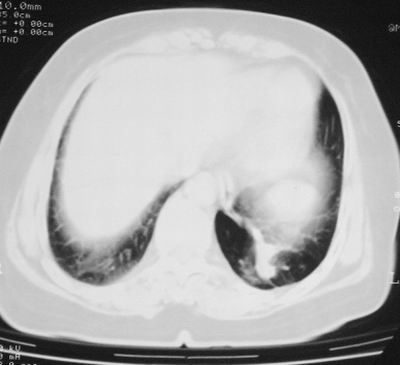

患者,女,64岁,4年前左腮腺"多形性"腺瘤手术治疗史.现复查胸部ct见左下肺块状影,该影与原左腮腺手术是否有联系?

本次复查胸部ct

左下肺软组织块影,有分叶、毛刺、空泡及胸膜牵拉征,左下肺周围性肺癌。

左肺下叶周围型肺癌,支持!(软组织肿块+分叶+毛刺+空泡+胸膜凹陷征)

左下肺软组织密度影,可见分叶,边缘可见毛刺征,胸膜增厚,强烈要求左下肺周围型肺癌

左下肺后基底段实性肿块,周围有毛刺,病变周围有肺气肿,与降主动脉间有条带状影相连,病灶4年前查体发现,纵隔内未见肿大淋巴结。考虑.肺隔离症,建议增强扫描与周围型肺癌鉴别。